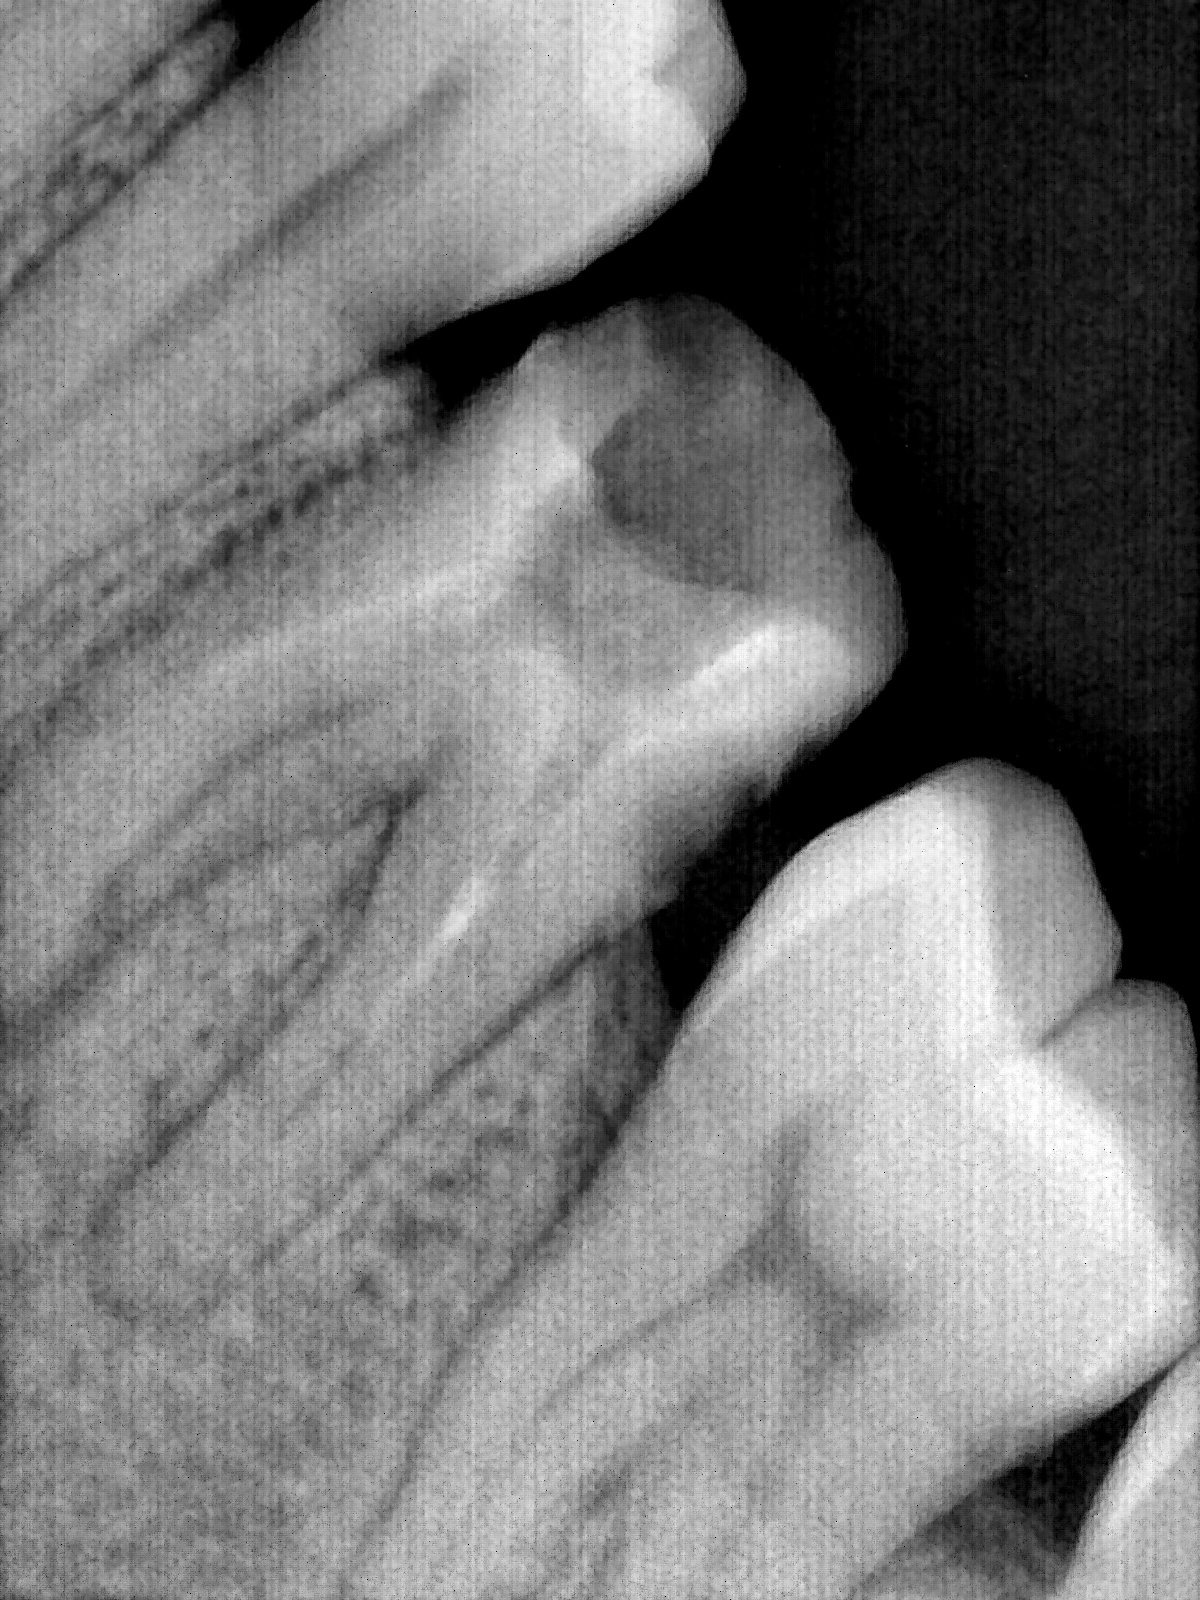

CR/DR 牙齿分割阶段记录

当前进展

- 完成了 CR/DR 牙齿相关分割训练

- 当前结果已经达到阶段预期,但仍有细节问题需要继续处理

相关测试

遇到的问题

- 训练过程中出现过 mask 下移问题

- 部分结果会出现 box 填充异常

- mask 边缘仍然有比较明显的锯齿感

参考

第三版算法分辨率效果比较

| 编号 | 原图 | 第一版 | 第二版 | 第三版 1216x1600 | 第三版 768x1024 | 第三版 1120x1120 |